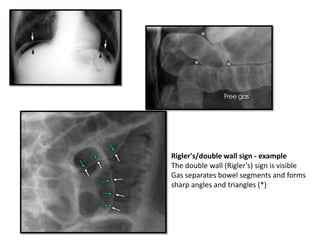

Rigler's/double wall sign - example

The double wall (Rigler's) sign is visible

Gas separates bowel segments and forms

sharp angles and triangles (*)